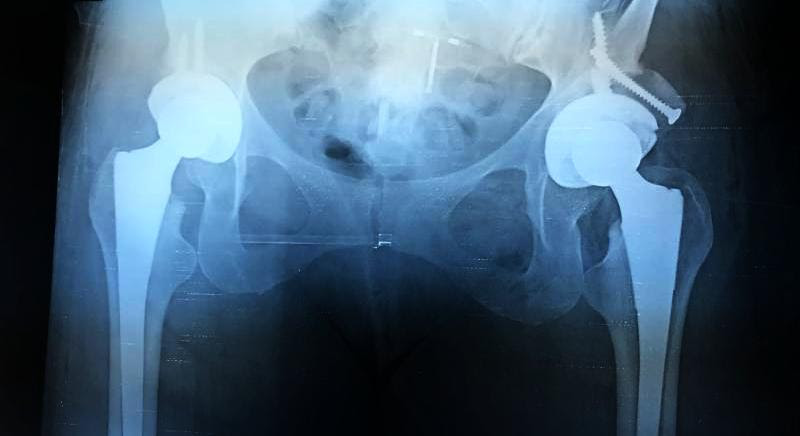

Both hips were replaced in one operation. This will make Marciela's recovery longer and more difficult but cuts the risks involved with having two surgeries. In order to have sufficient bone density in the left pelvis, part of Marciela's femoral head was used to create a bone graft to strengthen the area around the implant. As a result of the surgery Marciela's hips will now sit level making her legs an equal length.

The operations on both hips went well and Marciela is resting and looking forward to a successful recovery.